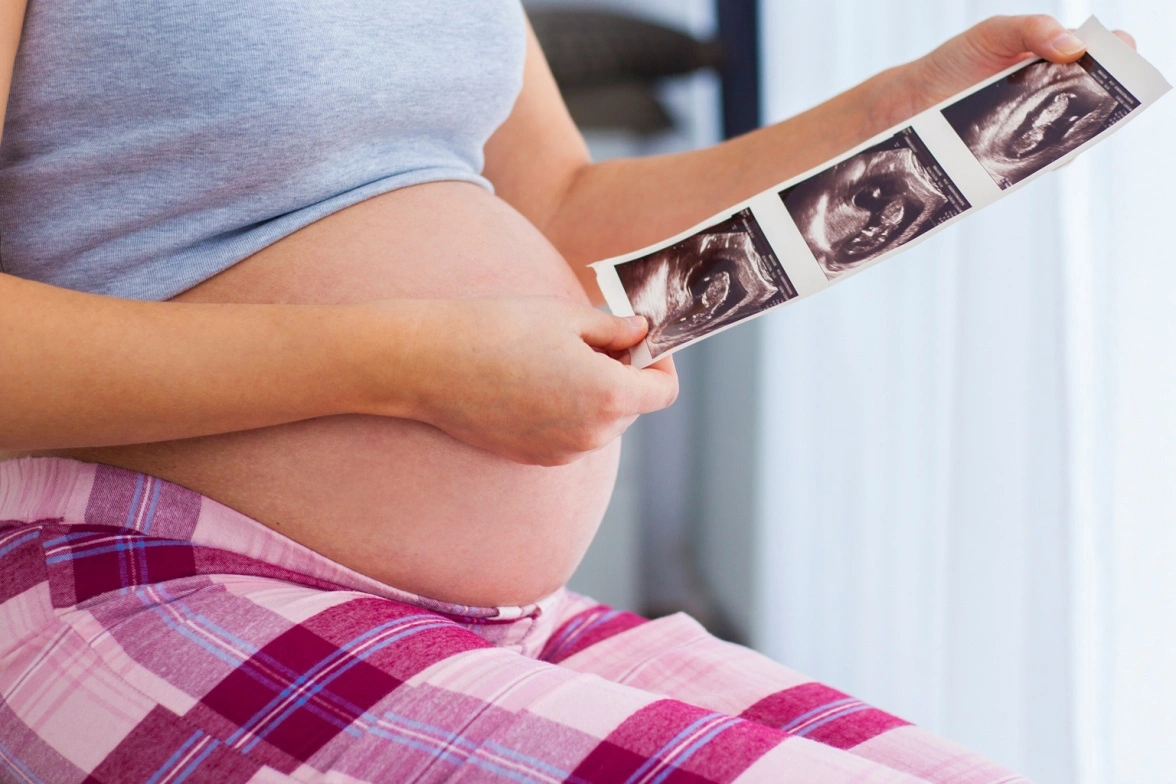

Pregnancy is the most beautiful and significantly life-altering event that one can ever experience. It’s a very precious time in your life. The Fetal Medicine solutions presents complete care for the unborn child. You can consult a fetal medicine specialist before while planning pregnancy, during pregnancy and after pregnancy. Dr. Neha Gupta is an expert in monitoring the growth and development of the fetus at every stage. Right from pre-pregnancy counseling, (in case you have some chronic medical disorder or difficulties in previous pregnancy) to managing the care during pregnancy or even, after the birth of the baby. We work in unison with your obstetrician and other specialists who are taking care of you and your baby after birth.

Our expert, Dr. Neha Gupta, is a highly qualified fetal medicine specialist. She has many years of experience in doing ultrasounds during pregnancy. She is not only trained in detection of abnormalities in the unborn child but will also counsel you how to approach further in the pregnancy. She is experienced in counseling the families in whom the future pregnancies (the unborn child) are at risk of developing hereditary diseases or helping those women who have some medical disorders which can affect the baby in the womb.